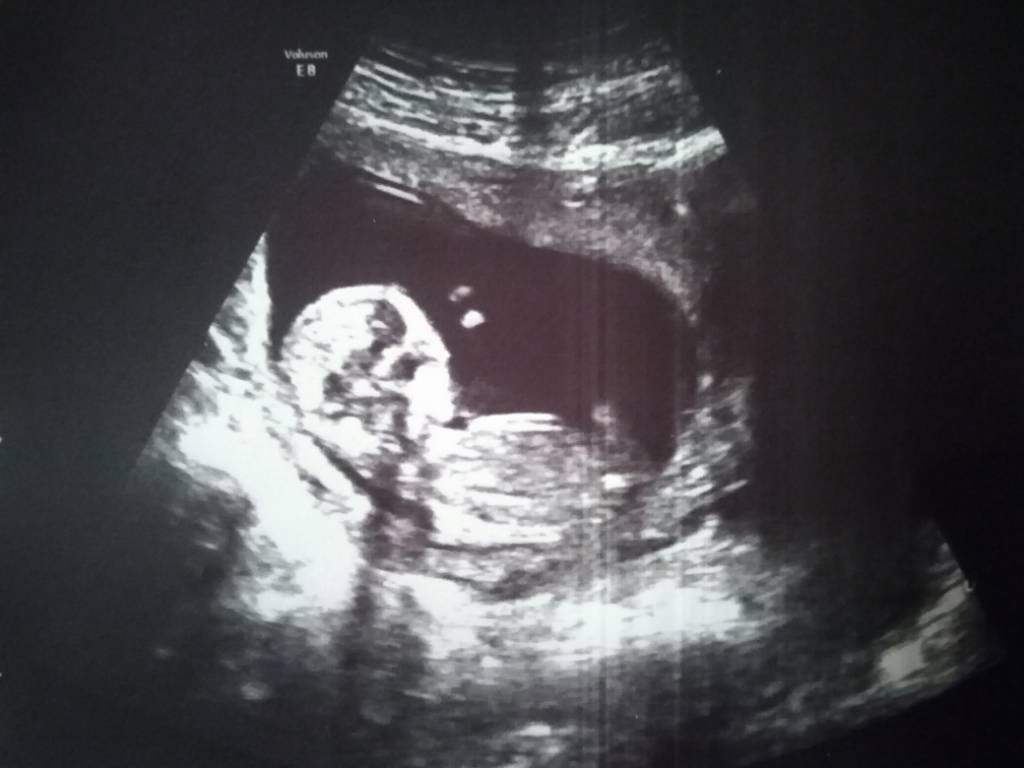

My już po prenatalnych. Dzidzia ma 6 cm. Wszystko wygląda dobrze. Bardzo ruchliwa była. Lekarz stawia na chłopczyka ale ja jeszcze wolę się do końca nie nastawiać. Najważniejsze że jest dobrze :) [emoji3531]

Ja też po widzę że idziemy równiutko ;) u nas też 6 cm serduszko jest, nogi ręce kość nosowa podobno też. A oprócz tego ku mojemu zaskoczeniu pomiędzy nogami póki co też coś urosło....